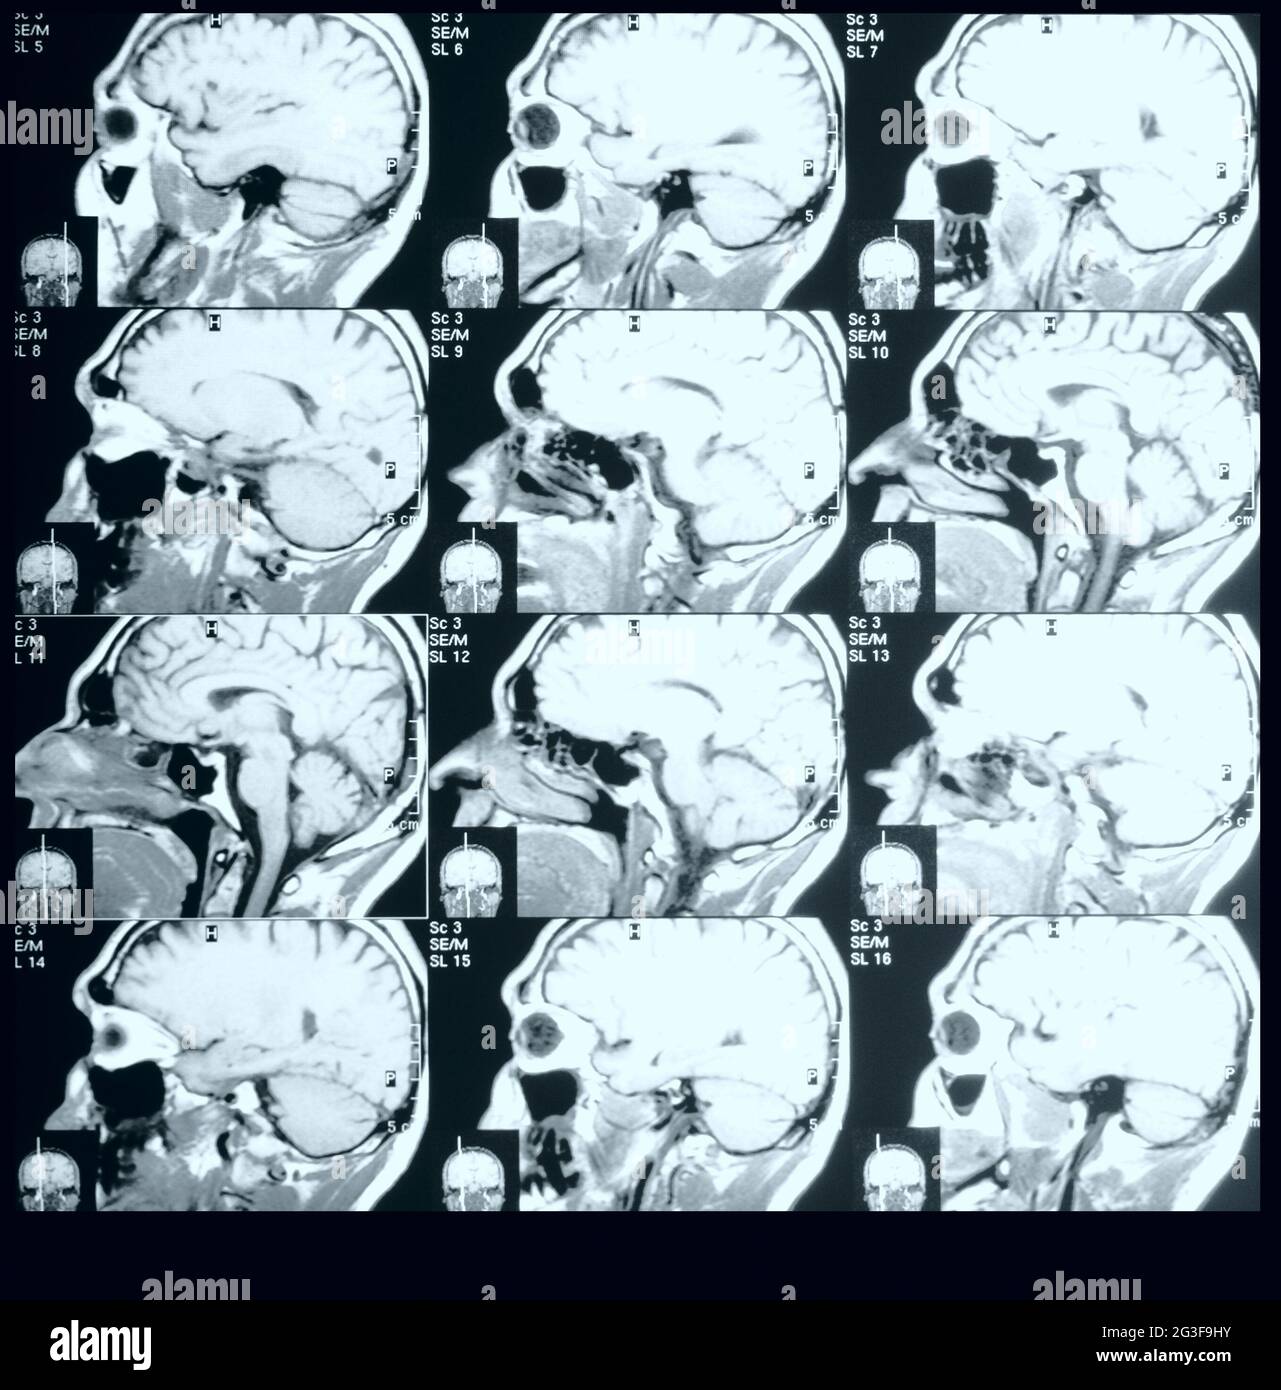

MRT Banque D'Imageshttps://www.alamyimages.fr/image-license-details/?v=1https://www.alamyimages.fr/mrt-image432440007.html

MRT Banque D'Imageshttps://www.alamyimages.fr/image-license-details/?v=1https://www.alamyimages.fr/mrt-image432440007.htmlRF2G3F9HY–MRT